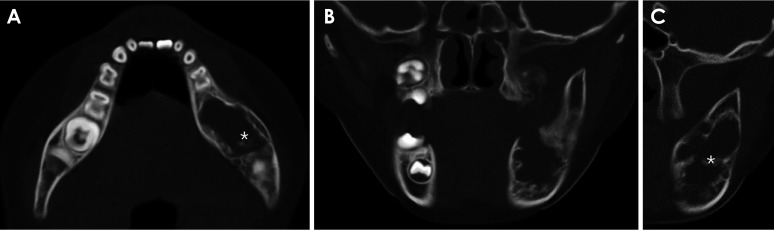

成釉细胞纤维牙本质瘤(AFD)是一种罕见的良性牙源性肿瘤,类似于牙本质发育不良的成釉细胞纤维瘤。本报告介绍了一例罕见的下颌骨纤维牙本质瘤病例,该病例为一名年轻患者,具有影像学特征。全景X光片和计算机断层扫描显示病变界限清晰,有内隔膜和钙化灶,导致相邻磨牙下移,颊舌侧皮质变薄,下颌后部扩张。手术通过肿块切除术切除了病灶,并在全身麻醉下拔除了患牙。在 5 年的随访期间,没有发现复发的迹象。AFD的放射学特征通常表现为中度到界限清楚的混合病变,具有不同程度的放射通透性,反映了牙本质形成的程度。当放射科医生在年轻患者的放射影像中发现多形性病变且几乎没有致密的放射通透性时,尤其是当病变伴有延迟萌出、嵌塞或缺失受累牙齿时,应将无牙颌畸形纳入鉴别诊断。

Ameloblastic fibrodentinoma (AFD) is a rare benign odontogenic tumor that resembles an ameloblastic fibroma with dysplastic dentin. This report presents a rare case of mandibular AFD with imaging features in a young patient. Panoramic radiography and computed tomography revealed a well-defined lesion with internal septa and calcified foci, causing inferior displacement of the adjacent molars as well as buccolingual cortical thinning and expansion of the posterior mandible. The lesion was surgically removed via mass excision, and the involved tooth was extracted under general anesthesia. During the 5-year follow-up period, no evidence of recurrence was observed. Radiologic features of AFD typically reveal a moderately to well-defined mixed lesion with varying degrees of radiopacity, reflecting the extent of dentin formation. Radiologists should consider AFD in the differential diagnosis when encountering a multilocular lesion with little dense radiopacity, particularly if it is associated with delayed eruption, impaction, or absence of involved teeth, on radiographic images of young patients.